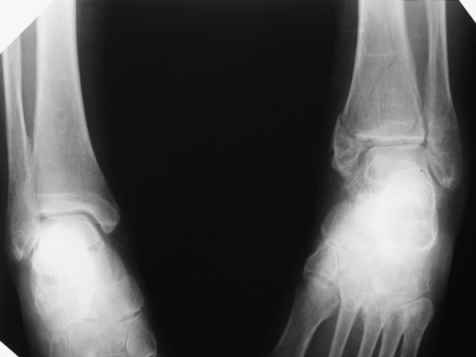

Огромное спасибо всем, кто участвует в обсуждении случая! Приношу глубочайшие извинения и участникам дискуссии и тем, чье внимание просто отвлек своим сообщением. В цейтноте получилось так, что на форум, необоснованно, отправил свои предварительные соображения. Хронология событий следующая. Пришла больная, на руках тот снимок в гипсе, который я выложил. Рассказала, что в 1999г. ломала на этой-же голени обе кости в средней 1/3. Травма тоже была неадекватно низкоэнергетическая - стояла на остановке, шагнула, оступилась - оскольчатые переломы обеих костей. Пластина на большеберцовую. Сросталось долго, линии перелома прослеживались на протяжении 5 лет. Теперешний перелом после того как оступилась в квартире.

Я порассуждал о том, что у нее есть, видимо, системные проблемы с прочностью костей и это МОЖЕТ СУЩЕСТВЕННО ПОВЛИЯТЬ НА ВЫБОР МЕТОДА ОПЕРАТИВНОГО ЛЕЧЕНИЯ, вплоть до артродеза. Предложил начать с замены гипсовой повязки и репозиции для уменьшения отека, столь ее беспокоившего. Которую и выполнил. При попытке R-контроля выяснилось, что кабинет в данный момент обесточен на неопределенный срок. Отправив больную домой я, некорректно по форме, материализовал свои соображения в виде предыдущего сообщения на Форуме.